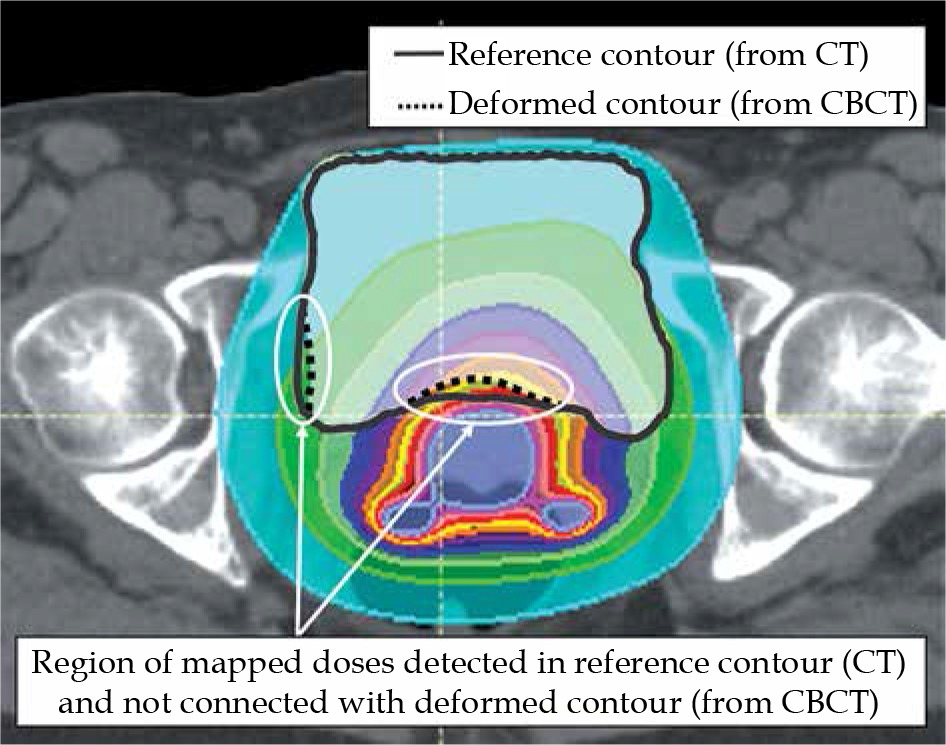

BRT doses initially associated with the CBCT image were transformed according to the registration results. Then, they were combined with the CT image (EBRT). Comparing doses in the bladder in CBCT and CT images, the highest compatibility was achieved in the transformation based on the biomechanical registration results (Reg_3). For 5 out of 10 observations, the discrepancy between doses was smaller than 5% (data patient 1, 6, 7, 9, and 10 in Figure 4). This confirms the observations made by Rigaud et al. [17]. Unfortunately, for 2 out of 10 observations, discrepancies were larger than 15% (data for patient 2 and 5 in Figure 4). It should be noted that the patients with observed discrepancies were marked with a substantial difference in bladder volume in CBCT and CT images, and relatively low DSC values (0.96) obtained with biomechanical registration (Reg_3). Low DSC values prove the inaccuracy in the alignment of bladder contours in the region where BRT doses are deposited. Therefore, prior to result acceptance, each image registration and contour propagation procedure as well as final dose distribution mappings should be visually evaluated. Figure 7 shows the result of dose mapping obtained for biomechanical registrations (Reg_3), which were characterized by various DSC values.